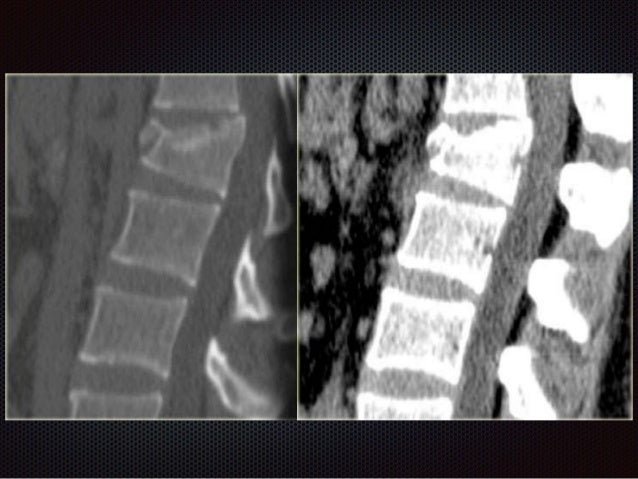

КТ ПОЗВОНОЧНИКА . ПЕРЕЛОМ ЗУБЧАТОГО ОТРОСТКА C7

Компрессионный перелом позвоночника - лечение.

Компрессионный перелом позвоночника

Рассмотрите возможность использования МРТ или КТ для получения более детальной информации о состоянии позвонка.